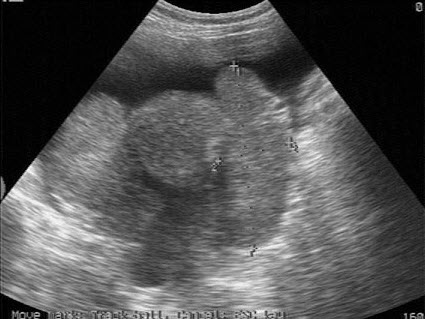

13、单项选择题

73、单项选择题

女性,28岁,停经46天,阴道不规则出血5天。血HCG68μg/ml。结合超声图像,最可能的诊断为()

A.畸胎瘤

B.附件炎性包块

C.子宫浆膜下肌瘤

D.宫外孕

E.囊腺瘤